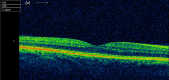

We report a very unusual presentation of primary intraocular lymphoma masquerading as anterior uveitis with atypical symptoms. A 68-year-old man, initially presented with a 4-day history of painless, left blurred vision. Examination revealed 2 or more anterior chamber cells, mutton-fat keratic precipitates and posterior synechiae. Treatment was initiated, the eye settled, and the patient was discharged. He re-presented 7 months later with hypopyon, a hazy cornea, fibrin deposits and a narrowed anterior chamber angle. Over the coming weeks, it became apparent that the temporal iris was thickened, involving the angle, and his intraocular pressure increased despite topical dorzolamide. Following advice from a tertiary centre and referral to a regional ocular oncology centre, a transscleral biopsy was performed and suggested a ciliary body melanoma. Enucleation was advised and performed, with histological examination revealing features consistent with an ocular diffuse large B-cell lymphoma not involving the optic nerve, sclera or cornea. This is the first ever published report of a case of ocular lymphoma masquerading in this way.